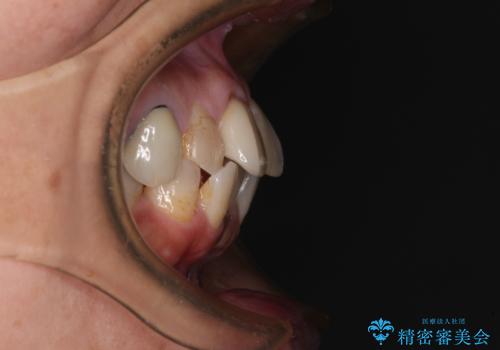

- 上下前歯のデコボコを気にして来院された患者様です。

歯列としては、ワイヤー装置でもインビザラインでも、どちらでも対応可能でしたが、処置されている歯が多く、ワイヤー装置を装着するためには処置歯のやり直しが必要な状態でした。

インビザラインでもアタッチメントを装着できないという同様のデメリットがありますが、比較的矯正治療を行いやすい歯列であったので、インビザラインによる矯正治療を行うこととしました。

術中や仕上がりに特に大きなトラブルはなく、スムーズに治療を終えることができました。